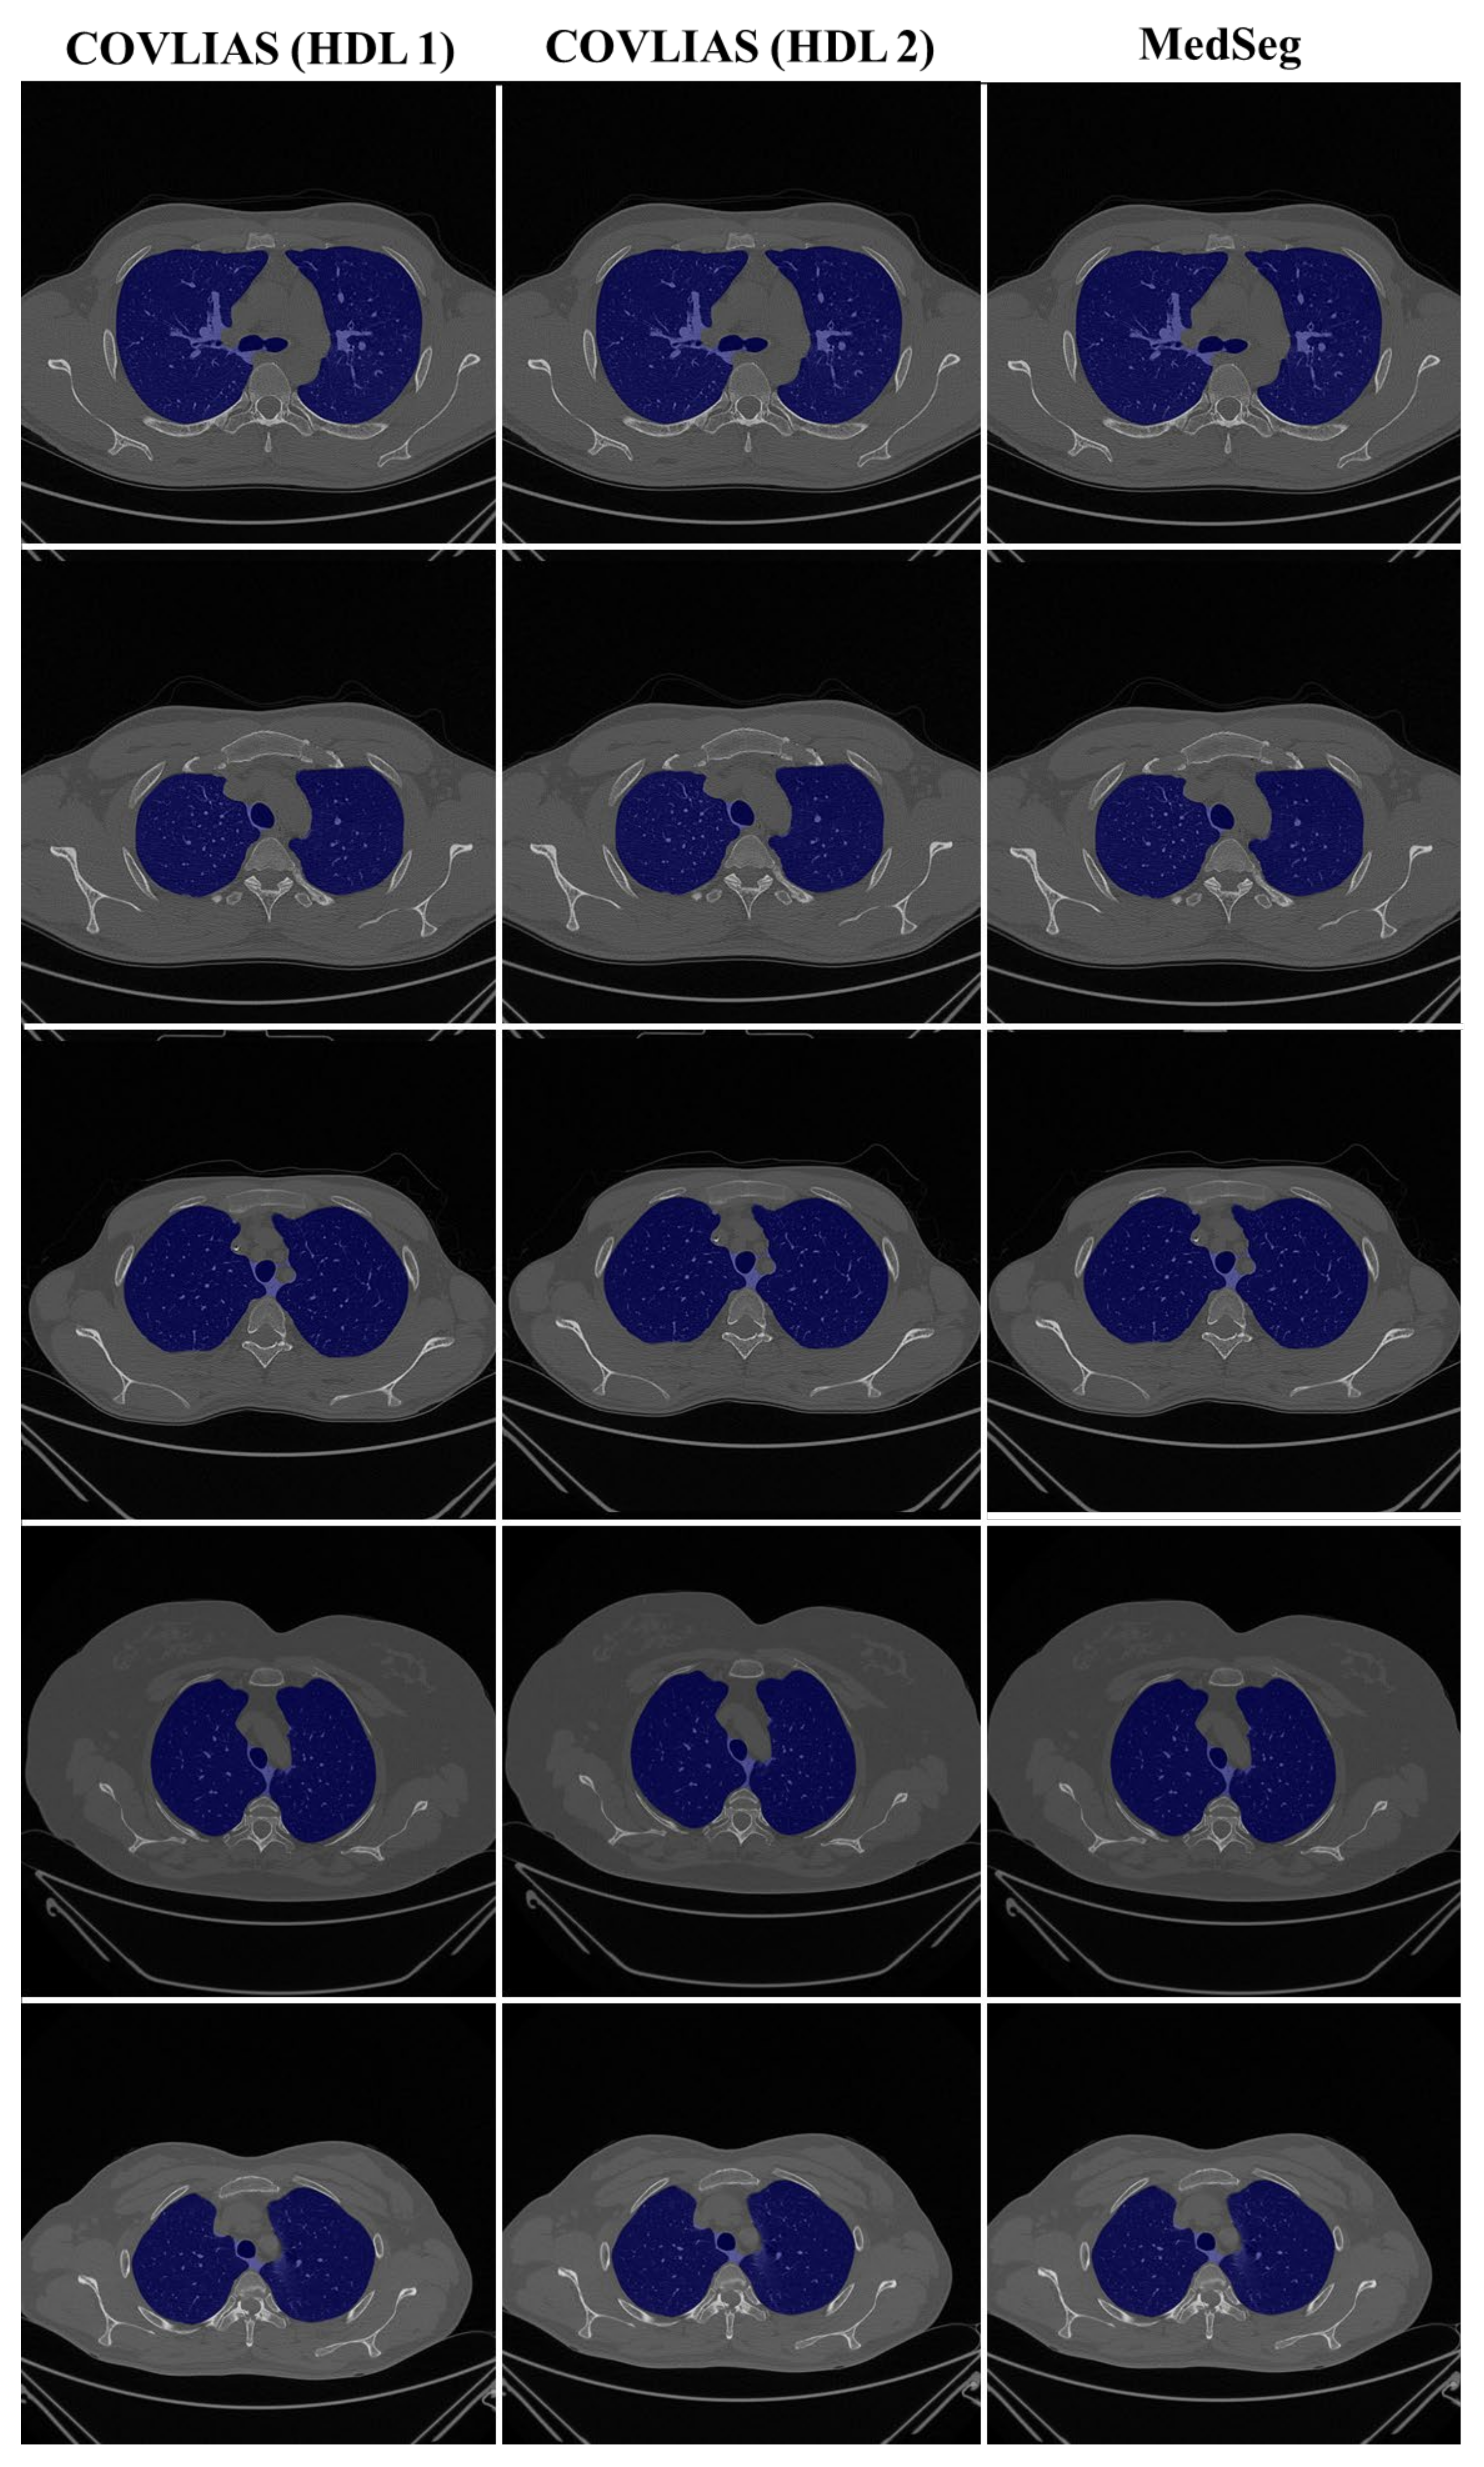

4.1. Performance: COVLIAS vs. MedSeg